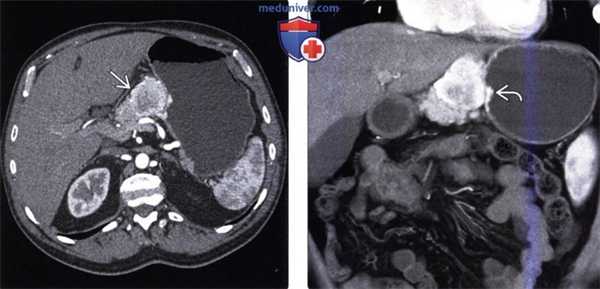

(Слева) На аксиальной КТ с контрастным усилением у мужчины 75 лет определяется в значительной степени васкуляризованное образование в желудочно-печеночной связке, непосредственно примыкающее к малой кривизне желудка.

(Справа) На корональной КТ с контрастным усилением (объемный рендеринг) у этого же пациента отчетливо определяется, что это образование вплотную прилежит к стенке желудка. При исследовании резектата было обнаружено, что образование является экзофитной карциноидной опухолью желудка. Кроме того, подобный внешний вид может иметь ГИСО желудка.